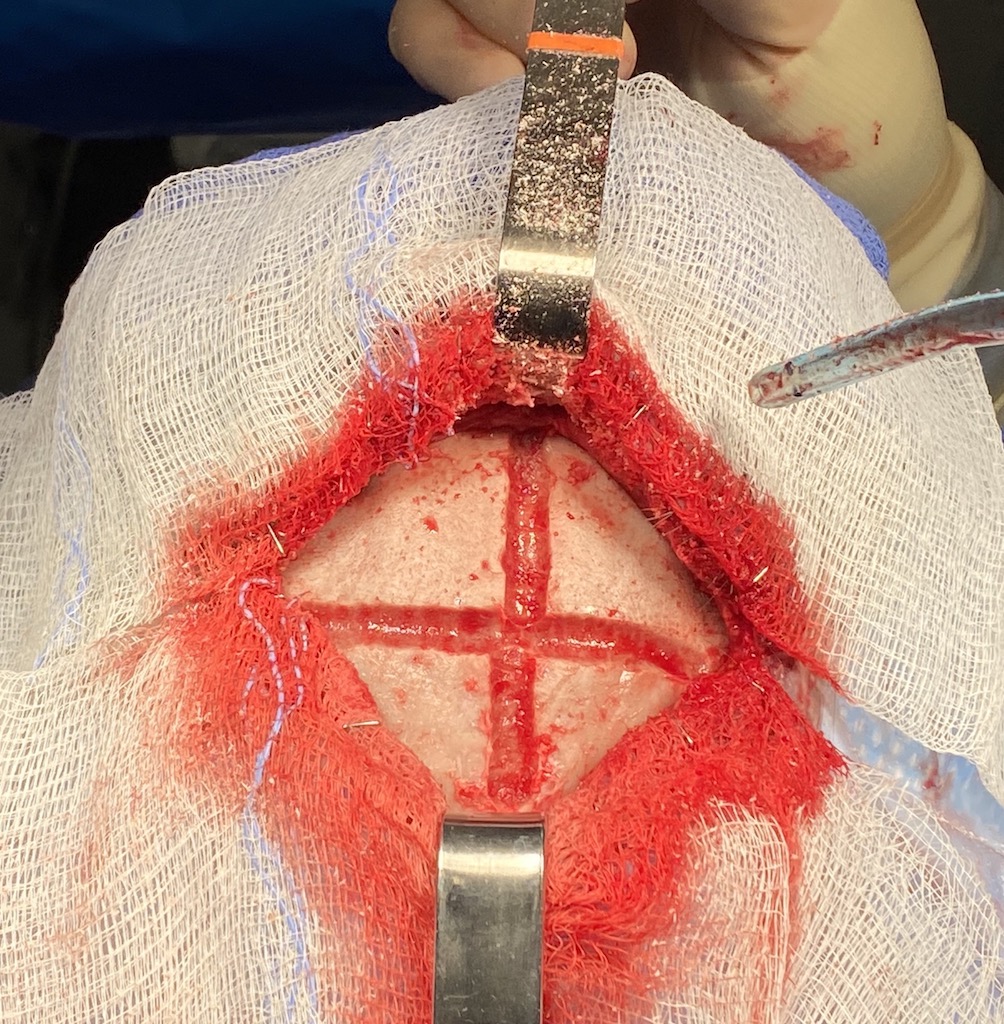

Patient 45

Desire for reduction in height of top of head.

Top of head skull reduction by removal of the outer cortical bone layered by a grid burring technique.